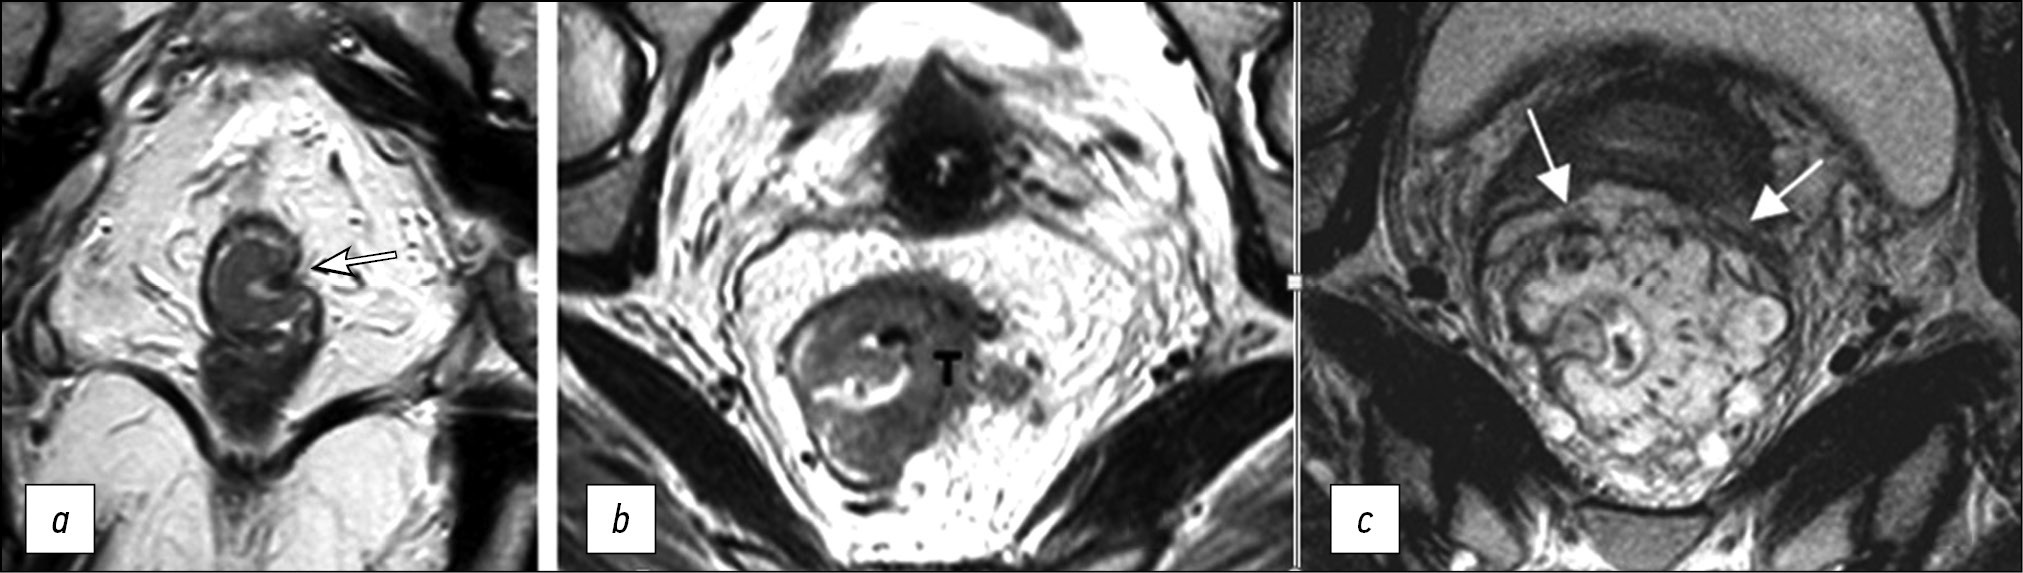

Mucinous cancer is a prognostically unfavorable histological variant of rectal cancer with tumor content of extracellular mucin >50% of the tumor volume. On MRI, mucin accumulations have a hyperintense signal on T2-WI (Fig. 3).

Fig. 3. Variants of tumor image on T2-WI. (a) Polypoid/exophytic tumor (arrow). (b) Semicircular tumor (T), extramural vascular invasion (arrows). (c) Mucinous tumor (arrows).

The tumor lesion is usually represented by ulceration/erosion in the center of the tumor, where the maximum depth of tumor invasion is determined.

Polypoid tumor is a tumor with an exophytic type of growth (Fig. 3). It may have a pedicle with clearly visible feeding vessels. The location of such a tumor can be indicated using a conventional dial (12 o’clock for the center of the anterior wall, 6 o’clock for the center of the posterior wall, 3 o’clock for the center of the left wall, and 9 o’clock for the center of the right wall).

A semicircular tumor occupies only part of the circumference of the rectum.

Circular/subcircular tumor spreads over the entire or almost entire circumference of the rectal lumen (Fig. 3).